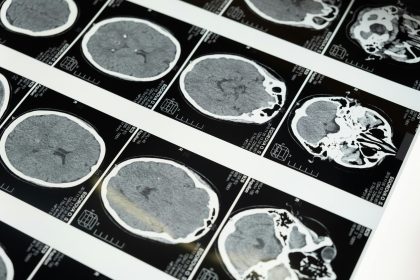

Biomarkers and Emerging Diagnostic Tools in Brain Injury

Explore how blood biomarkers, advanced imaging, and AI tools are transforming brain injury diagnosis for faster, more accurate detection.

How Doctors Diagnose a Brain Injury

Learn how doctors diagnose brain injuries — neurological exams, CT, MRI, and specialized tests. Early diagnosis improves treatment and recovery…